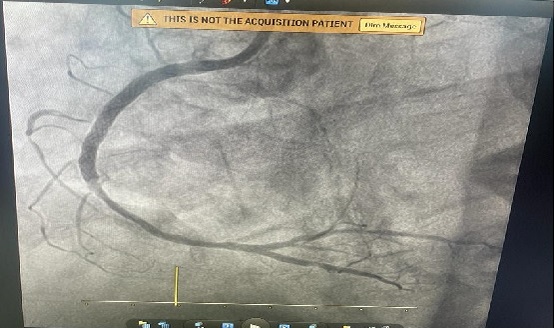

CASE 13- PTCA TO LCX CASE

Critical angioplasty of 86 years age patient done successfully.

Ptca to Lcx 2.75x26/RCA 3x38 mm Medtronic onyx stents.